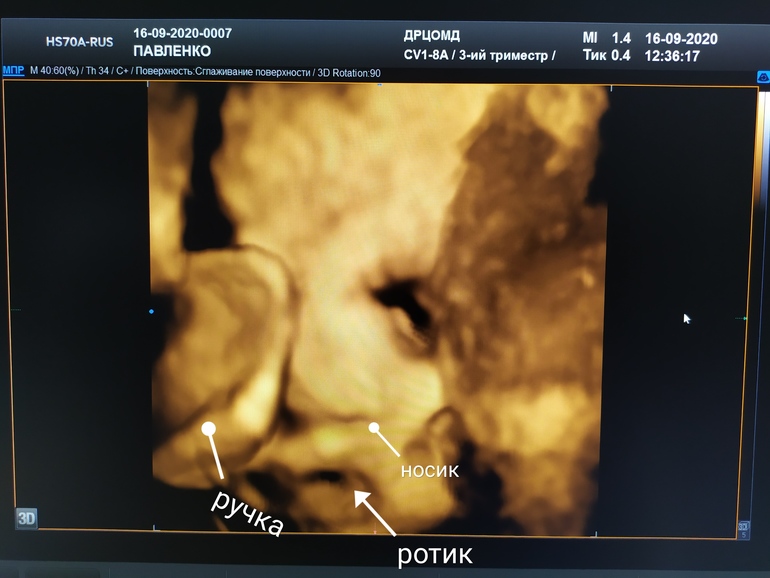

Была сегодня на скрининге) Плацента поднялась, доктор сказал, что необходимо ещë 3см до отлично, но с 20 до 41 - это тоже хороший результат👍😉 Девочка осталась девочкой😍 мы отличная девчачьим команда! Мои ощущения, будто она прыгает по дну - это, в общем, не впечатления - прыгает ляля, видела сладкие пяточки))) расположена ножками вниз, нужно как-то еë перевернуть иначе КС. На это ещë целых 10,5 недель, так что есть чем заняться💪 Кушает хорошо) вес на верхней границе нормы - сладкое сократить😅 воды в норме. Показатели хорошие. А ещë она вообще не любит посторонних. Все предыдущие спинные скрининги были намëком, сегодня откровенно закрылась ручками😆 правда, добрый доктор заморочился, понаблюдал и нашëл нам часть личика😍 подписала, потому что папочка спросил как правильно рассматривать эти пятнышки🤣🤣🤣